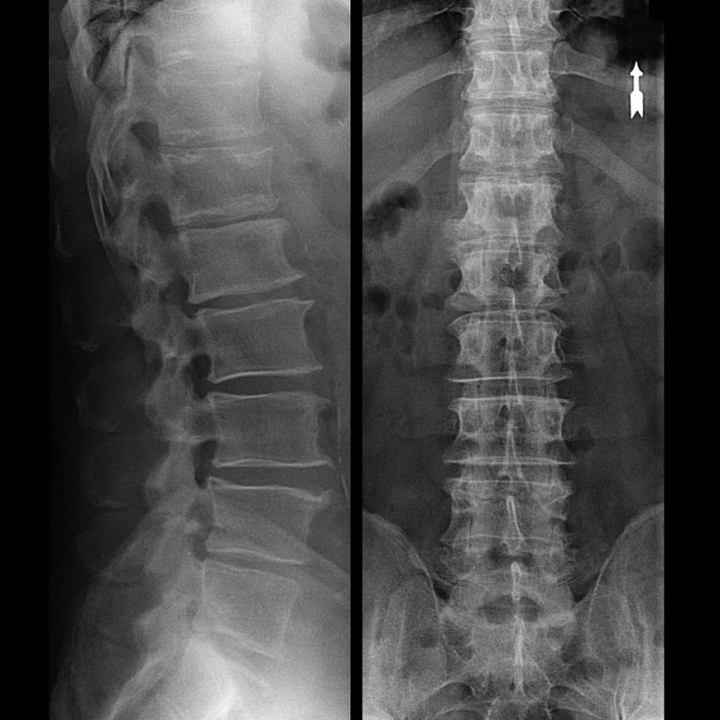

| Graden | Radiografische borden |

| De eerste | De veranderingen zijn niet uitgesproken. De gewrichtsspleten zijn matig, ongelijkmatig versmald, er is geen vernietiging van het oppervlak van het dijbeen. Kleine benige gezwellen worden waargenomen aan de buiten- of binnenrand van het acetabulum |

| De seconde | De hoogte van de voegruimte wordt aanzienlijk verminderd vanwege de ongelijke versmelting. De benige kop van het dijbeen wordt naar boven verplaatst, vervormd, vergroot, de contouren worden ongelijk. Botachtige gezwellen vormen zich op het oppervlak van de binnen- en buitenranden van de glenoïd fossa |

| Derde | Er is een volledige of gedeeltelijke versmelting van de gewrichtsruimte. De heupkop is sterk geëxpandeerd. Meerdere benige gezwellen bevinden zich op alle oppervlakken van het acetabulum |

Bij het stellen van een diagnose houdt de arts rekening met de klinische manifestaties van pathologie, anamnese, de resultaten van een extern onderzoek van de patiënt en instrumentele onderzoeken. Radiografie is het meest informatief. Met zijn hulp wordt de toestand van het heupgewricht beoordeeld, het stadium van het beloop, de mate van schade aan het kraakbeenweefsel en in sommige gevallen wordt de oorzaak van de ontwikkeling vastgesteld. Als de cervico-diphyseale knoop is vergroot en het acetabulum schuin en afgeplat is, is het met een hoge mate van waarschijnlijkheid mogelijk om dysplastische aangeboren veranderingen in de articulatie aan te nemen. De ziekte van Perthes of juveniele epifysiolyse wordt aangegeven door de verstoorde vorm van het heupbot. Radiografie kan posttraumatische artrose aan het licht brengen, ondanks het ontbreken van een eerder trauma in de anamnese. Andere diagnostische methoden worden ook gebruikt: